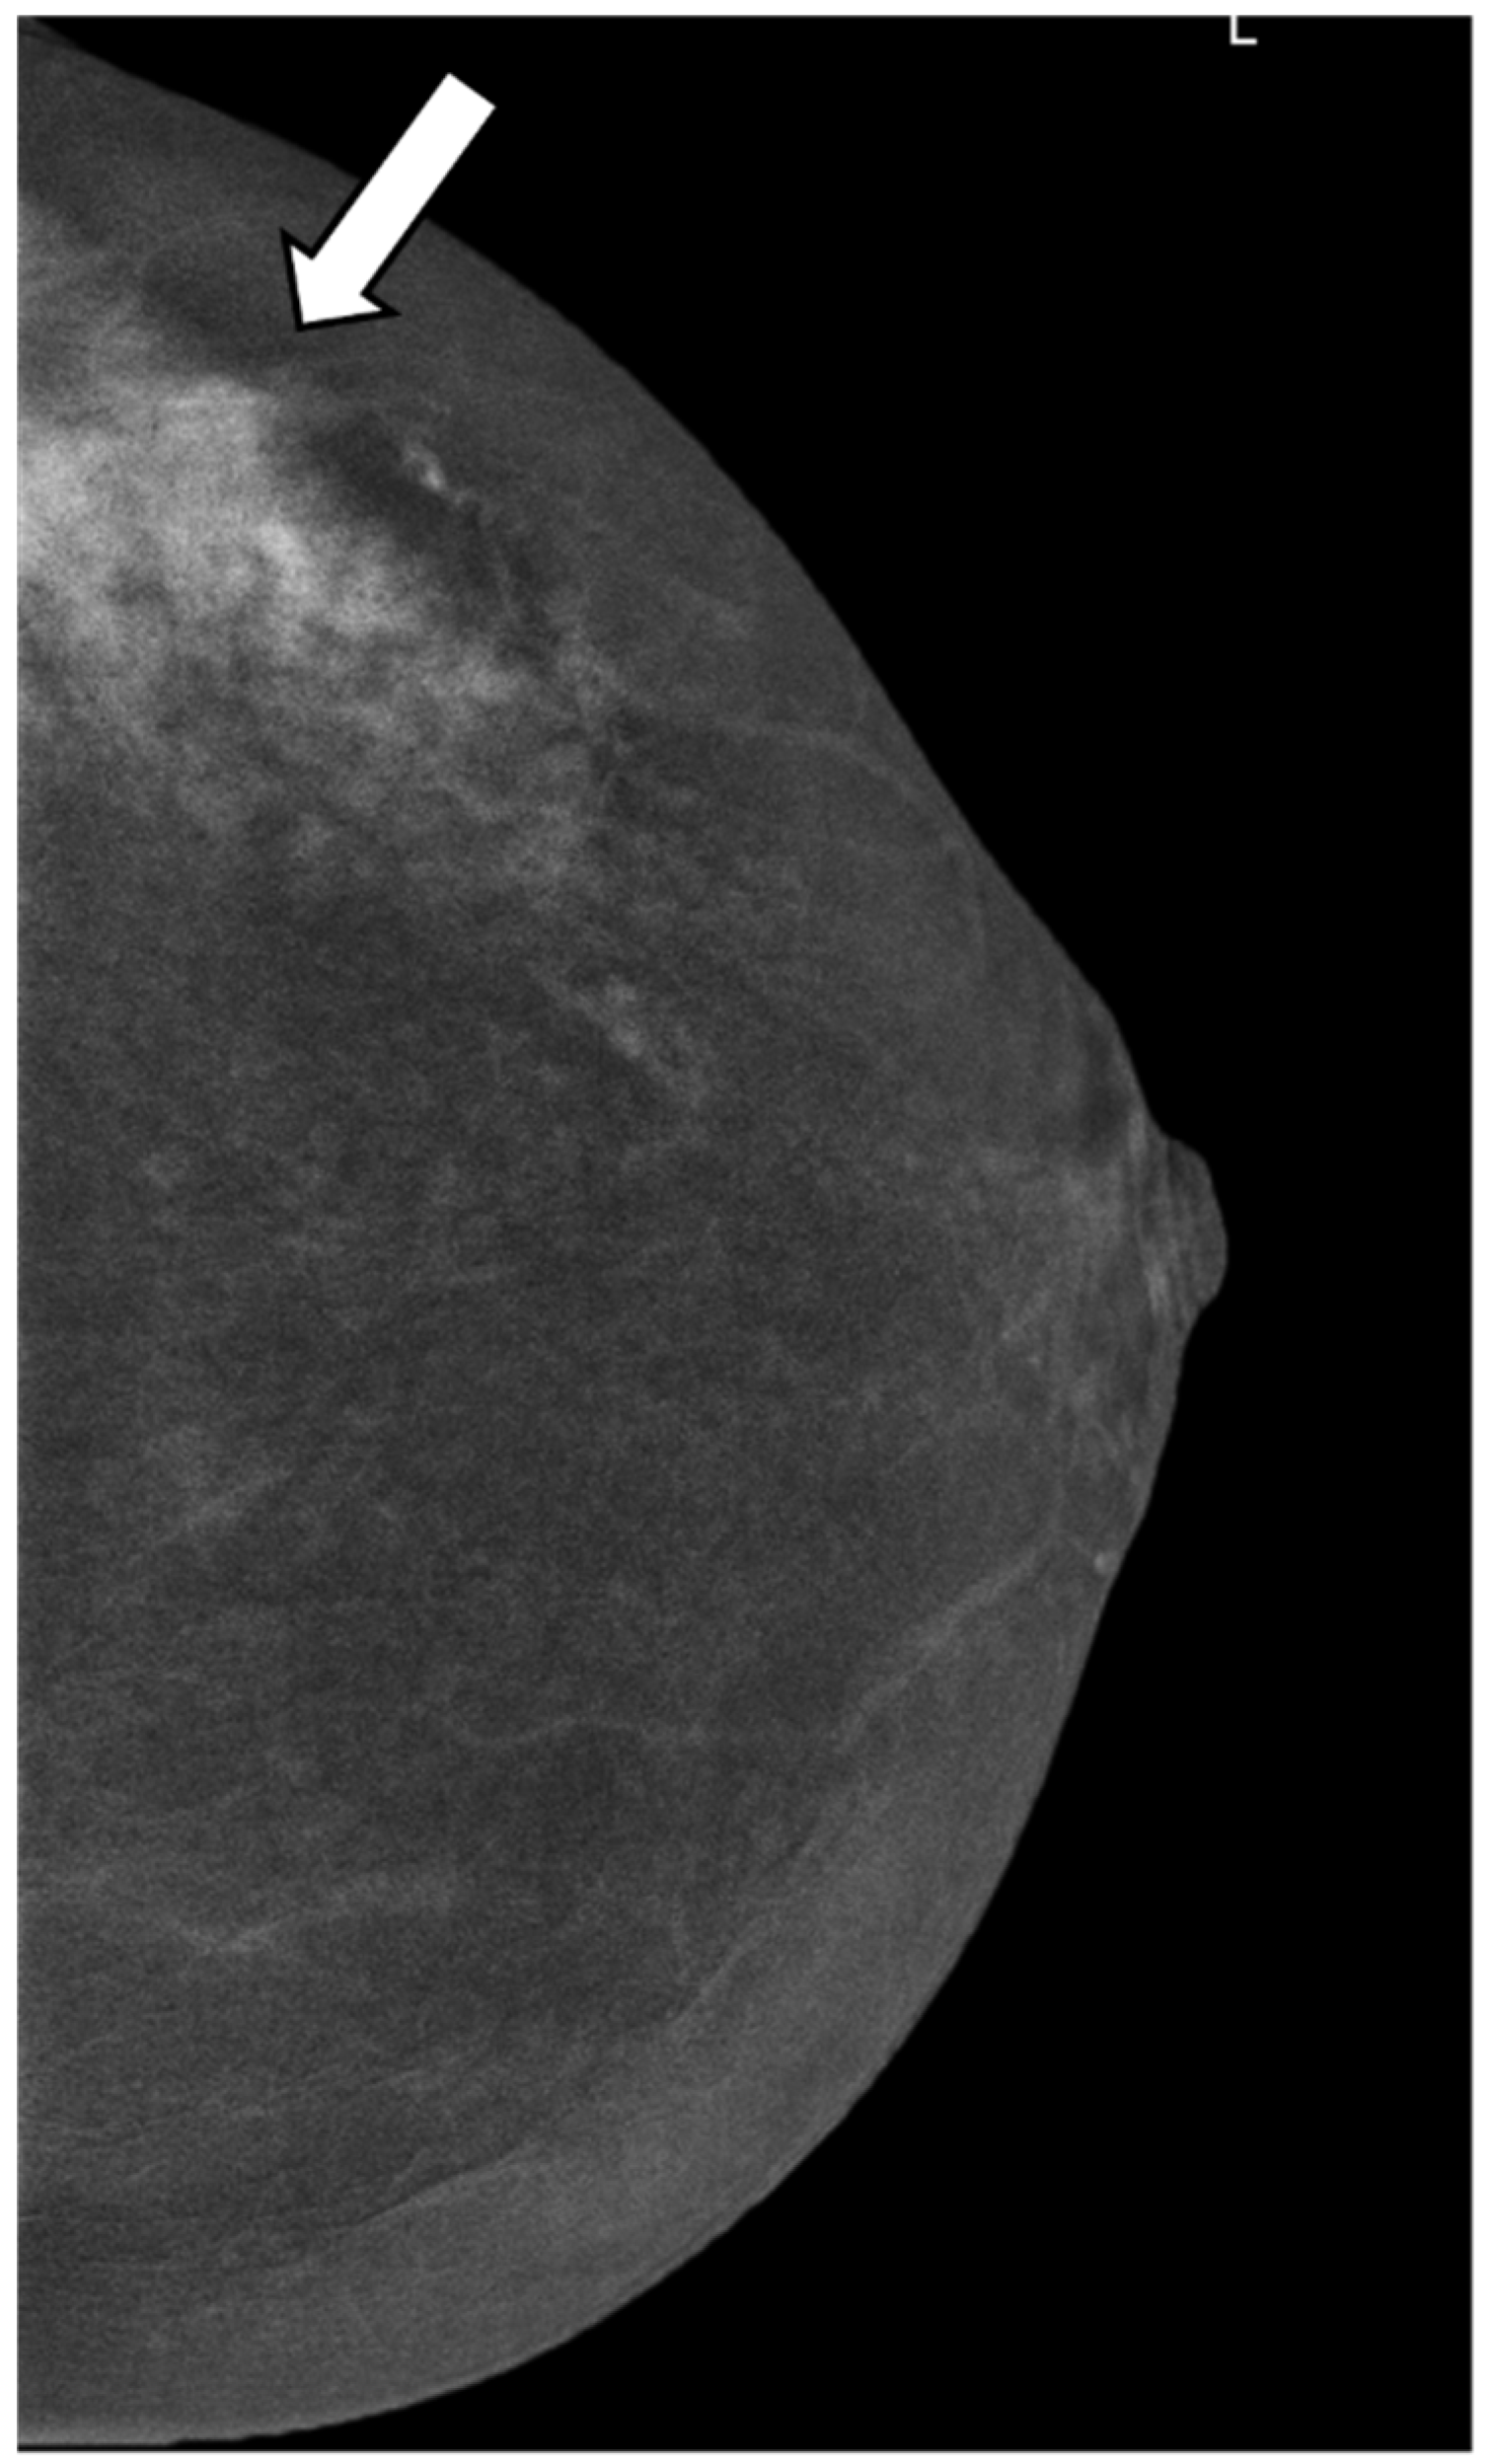

A Score to Predict the Malignancy of a Breast Lesion Based on Different Contrast Enhancement Patterns in Contrast-Enhanced Spectral Mammography